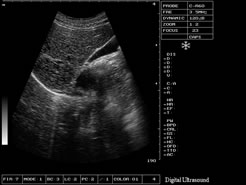

> 全數(shù)字成像技術(shù)應(yīng)用

> 大容量電影回放及永久性圖像存儲

永久存儲:128幅圖像永久存儲,自動生成報告頁面;

電影回放:256幅圖像循環(huán)顯示或逐幅查看